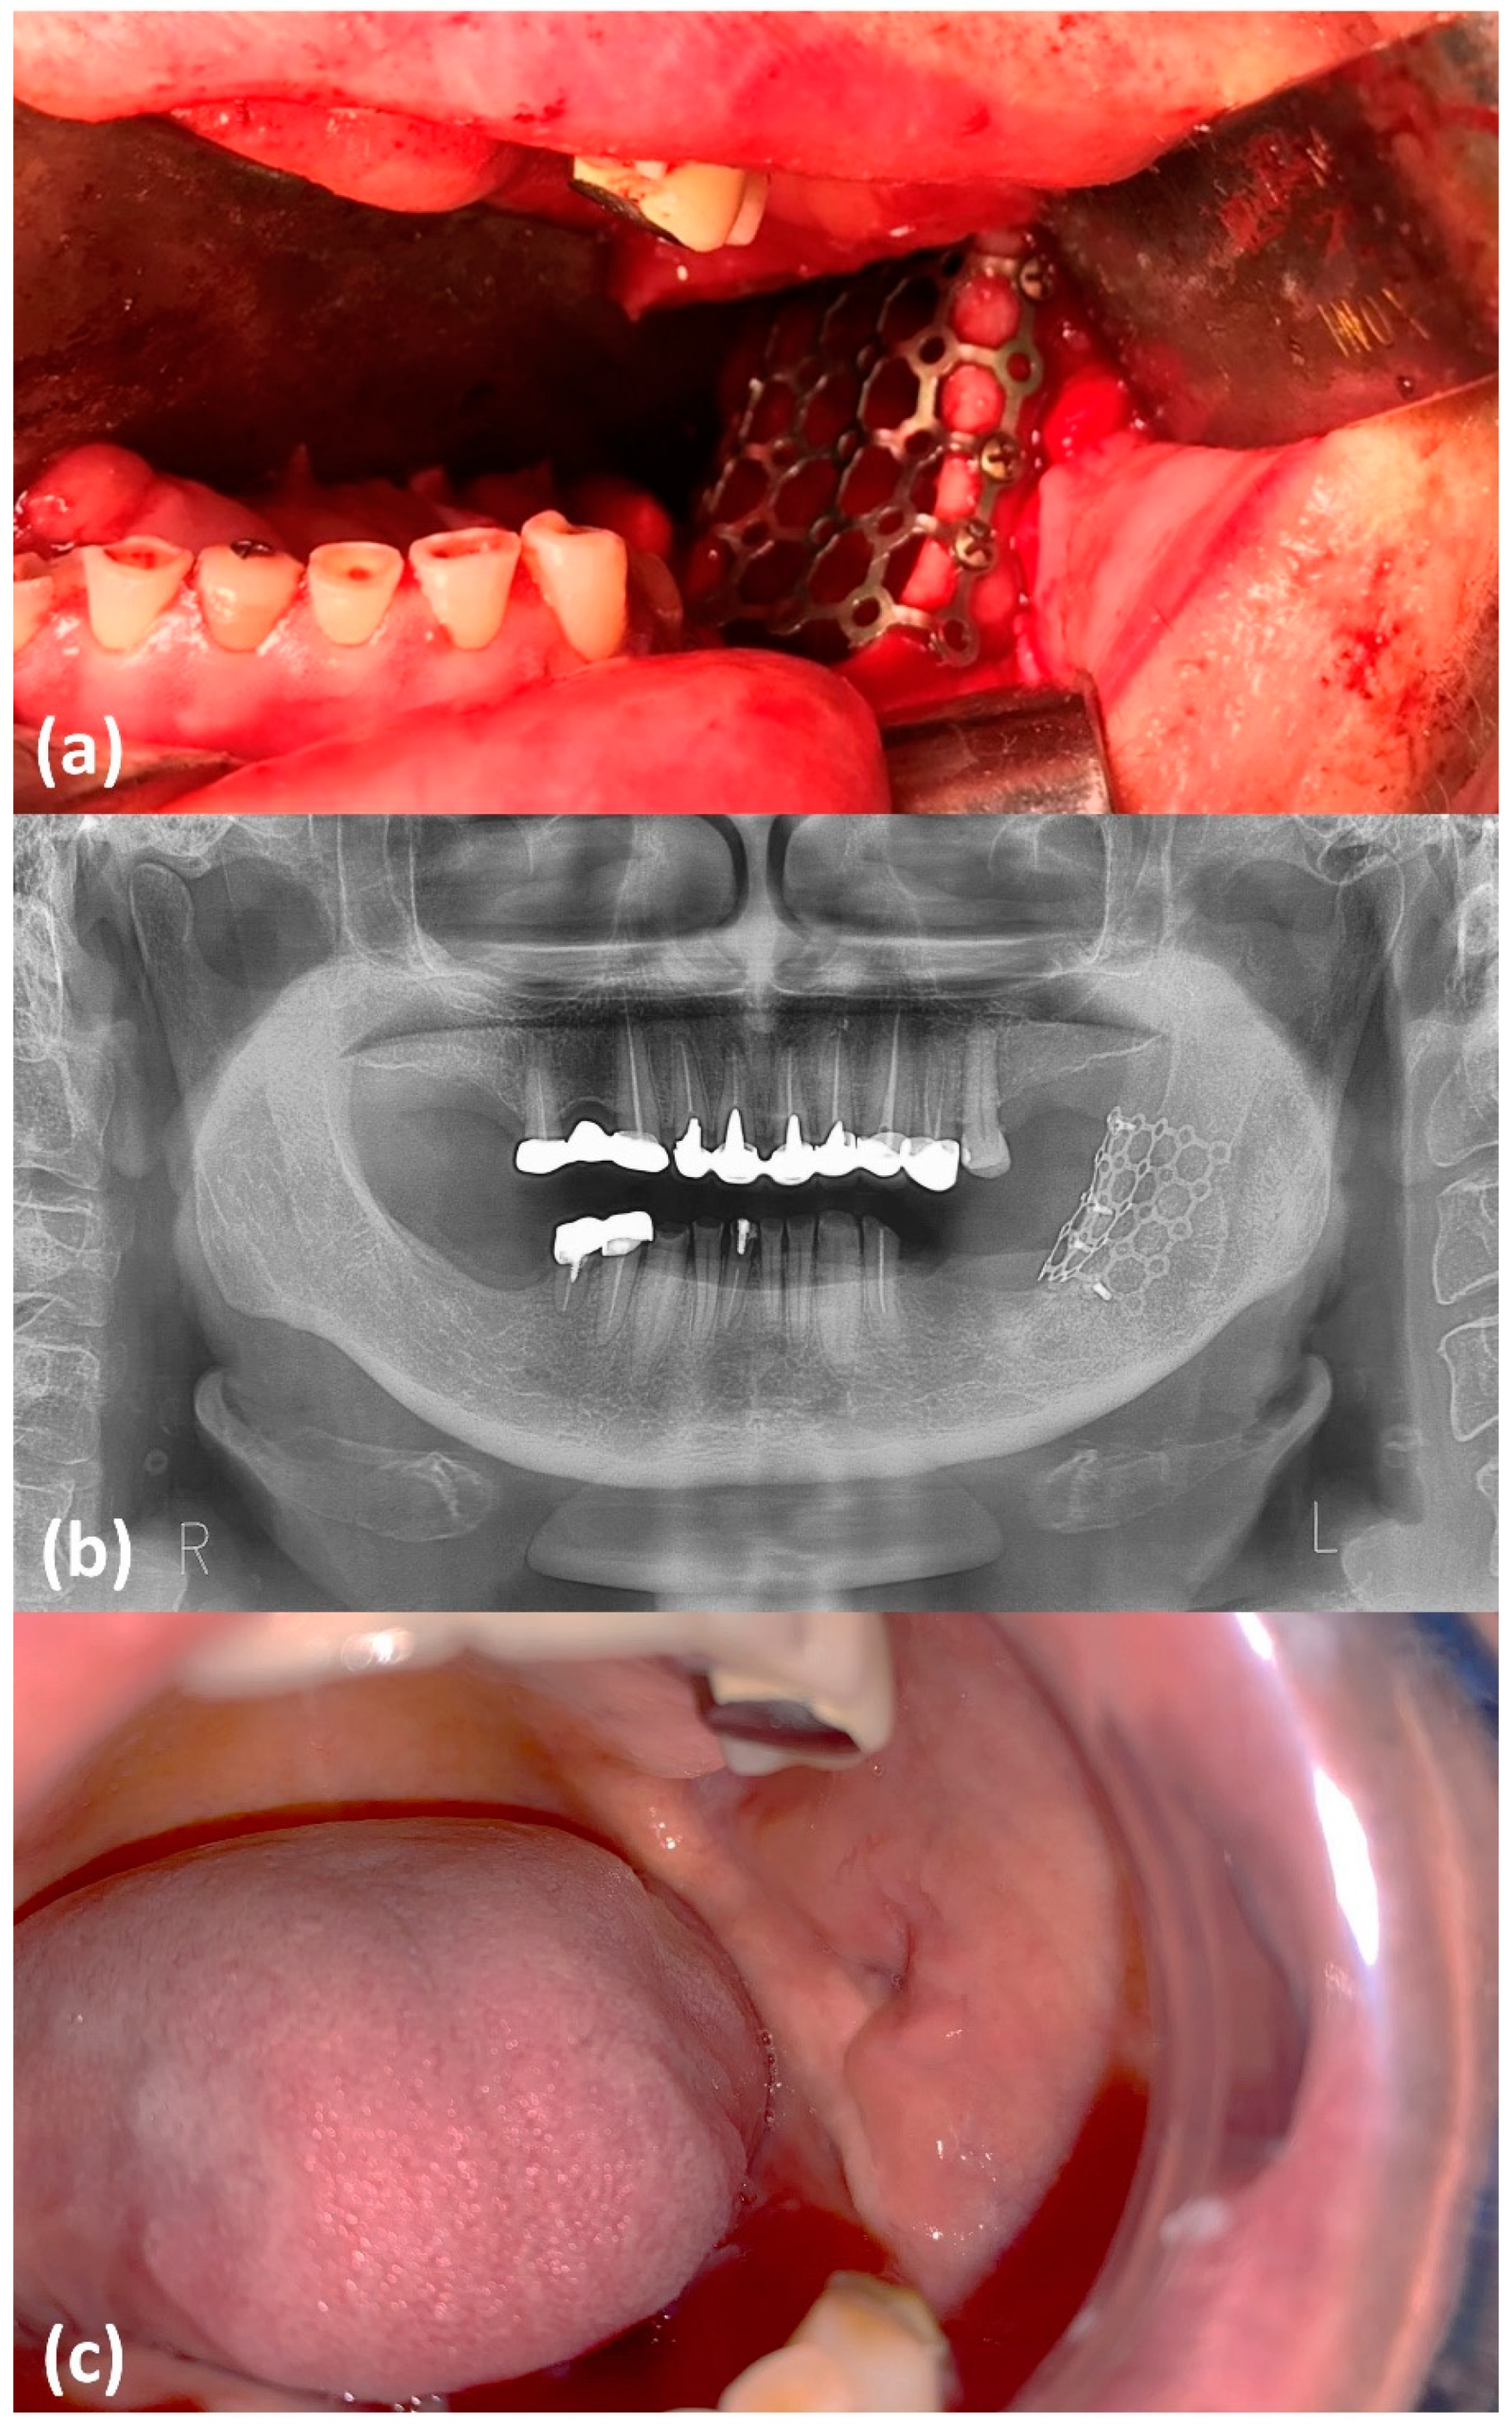

2. Case Report